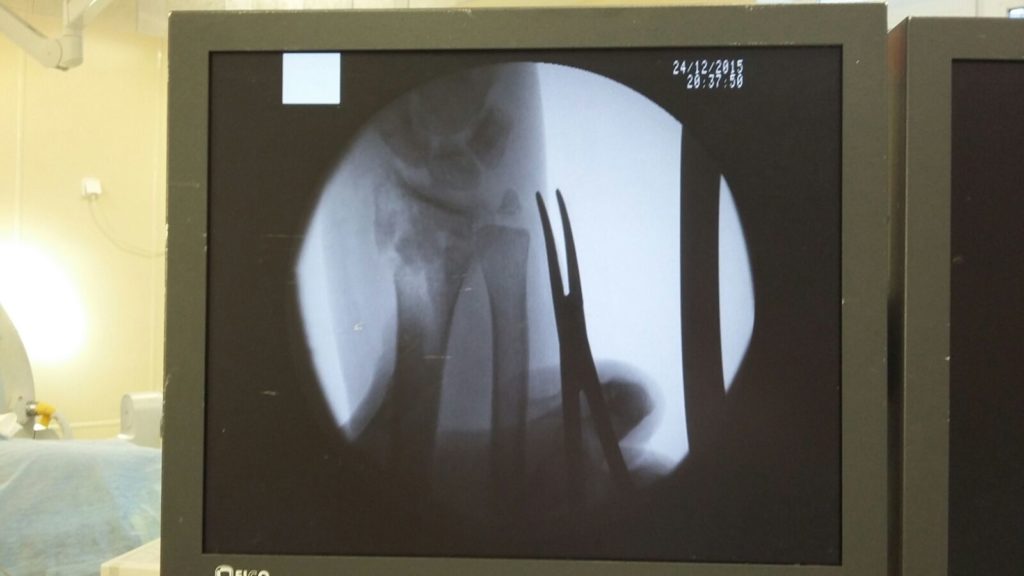

Операция - открытая репозиция, остеосинтез лучевой кости пластиной с костной ксенопластикой материалом "Остеоматрикс". На контрольных снимках в три месяца имеется консолидация перелома, миграции фиксатора нет, имеется остеоинтеграция ксенопластического материала.